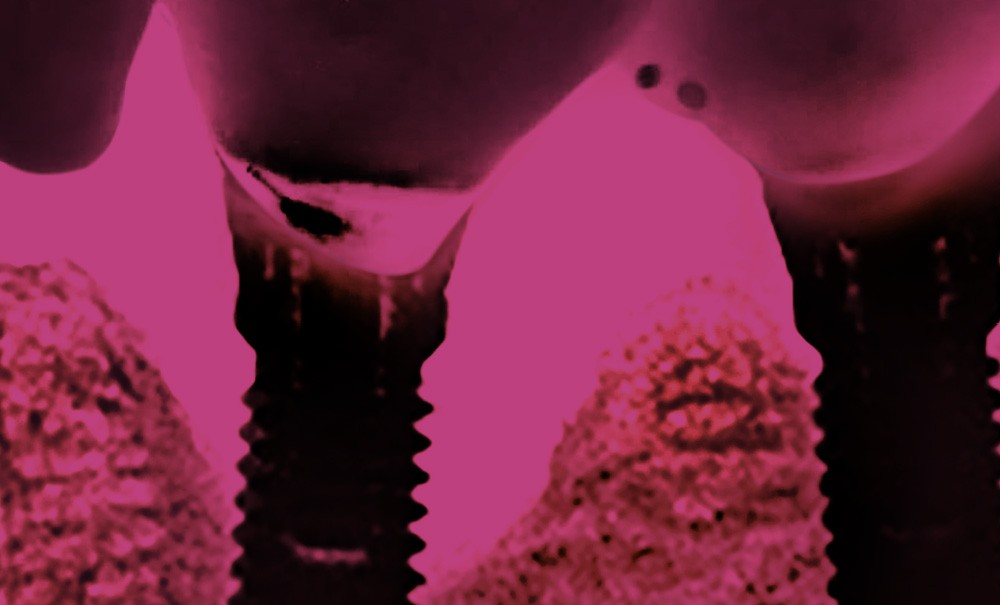

Le traitement des péri-implantites

Dans cette édition spéciale, onze articles et 17 auteurs font le point sur les thérapeutiques d’une pathologie de plus en plus présente dans le quotidien des chirurgiens-dentistes : les péri-implantites. Outre la prévalence, les facteurs de risque et les traitements, ils abordent également des sujets qui incitent à la réflexion. Car de nombreuses incertitudes persistent quant à cette pathologie aux origines désormais bien plus souvent biologiques que mécaniques.